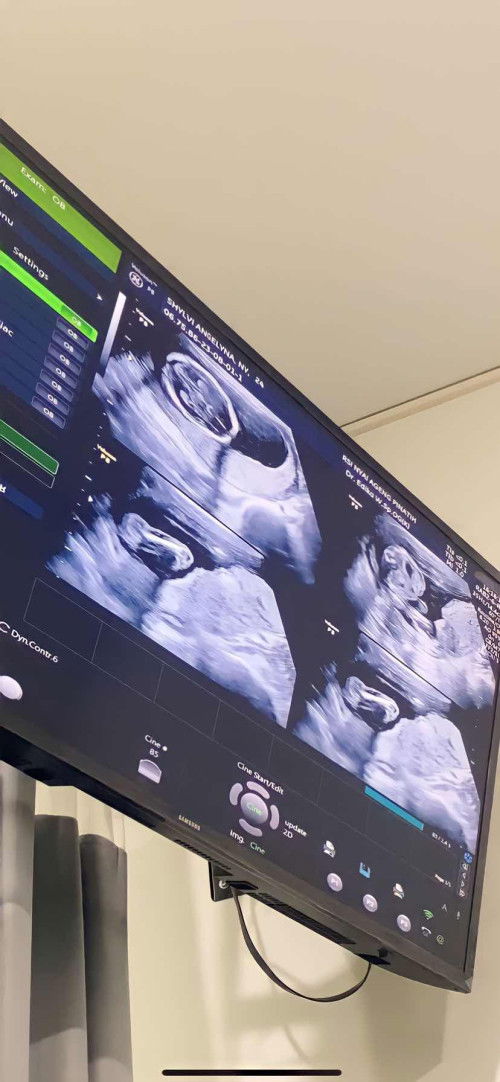

Hasil usg 17 minggu

Doain ya bun janinku sehat" terus dan berkembang tampa kurang satupun. Ini hasil usgku di 17 week kehamilan pertama. Berat badan 260gr. Jk nya belum keliatan krna posisinya nutupin. Alhamdulillah kata dokter semua normal🥰